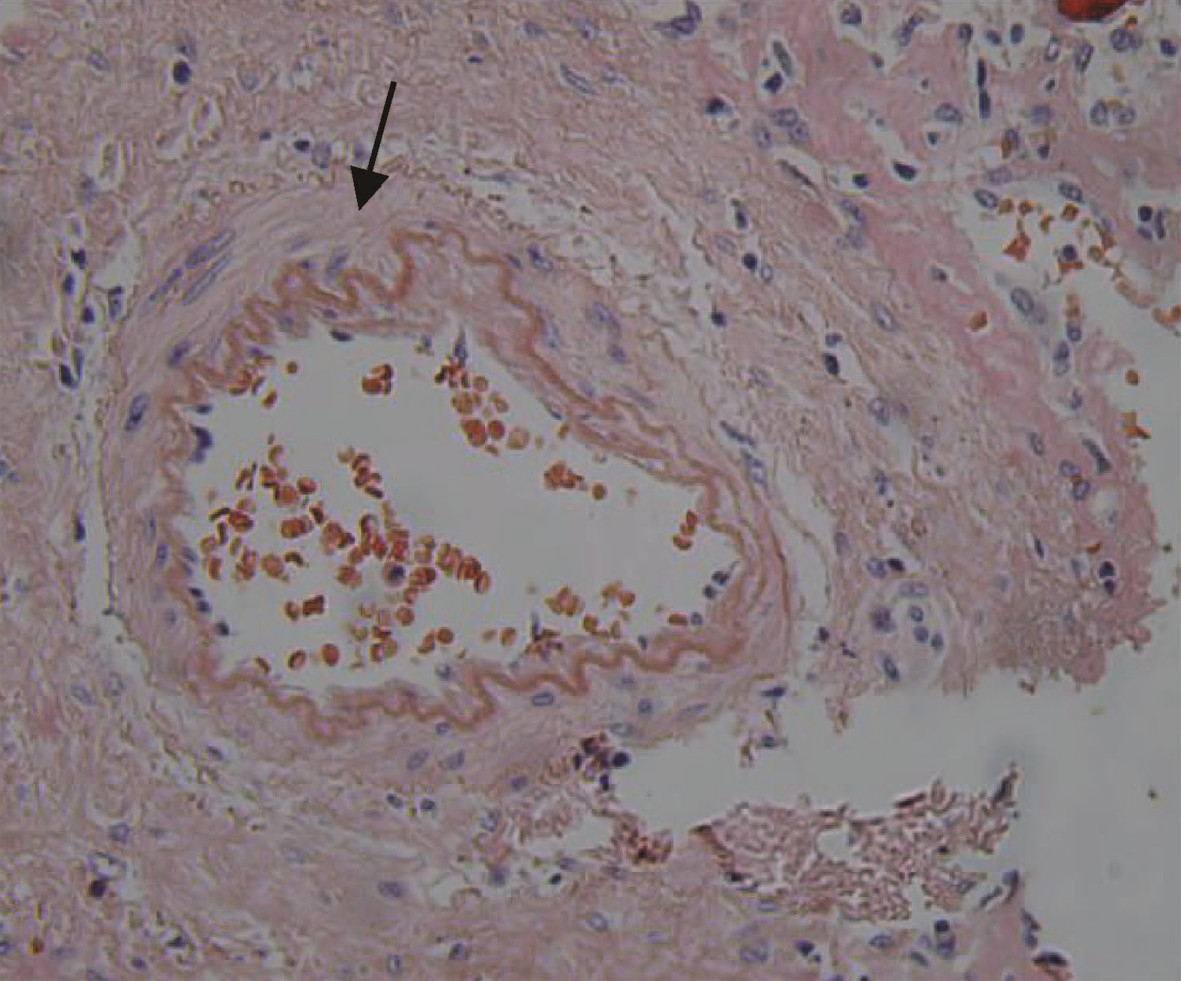

肝细胞癌合并胆管癌栓1例报告

2022, 38(8): 1872-1874. DOI: 10.3969/j.issn.1001-5256.2022.08.028

摘要(803) HTML (455) PDF (3665KB)(82)